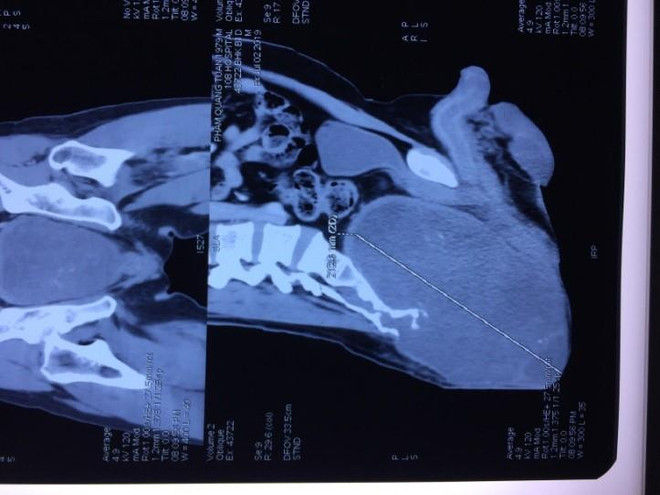

Cắt khối u khổng lồ vùng xương cùng cụt cho một bệnh nhân ảnh 1Phim chụp khối u của bệnh nhân. (Ảnh: PV/Vietnam+)

Ngày 7/10, theo thông tin từ Bệnh viện Trung ương Quân đội 108, các bác sỹ của bệnh viện đã phẫu thuật thành công, cắt khối u khổng lồ vùng mông, với kích thước 15x14x20cm cho một bệnh nhân.

Qua thăm khám, các bác sỹ khoa Chấn thương Chỉnh hình Cột sống chẩn đoán bệnh nhân mắc bệnh u nguyên sống (Chordoma) khổng lồ vùng cùng cụt, khối u phát triển ra cả phía trước xương cùng, đè đẩy rất nhiều vào bóng trực tràng và bàng quang.

Khối u gây biến dạng lớn, khiến bệnh nhân không ngồi thẳng và nằm ngửa được từ một năm nay.